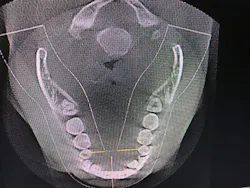

Figure 4: Maxillary and mandibular retrusion.

Figure 8: Deviated nasal septum and narrowed airway

Figure 9: 95% obstructed posterior airway due to extremely enlarged tonsils

After identifying Danny’s history and evaluating the clinical signs, we moved to screening and testing. We recommended a home sleep test for his airway and breathing problems, as well as a Doppler auscultation and CBCT imaging for the TMD and occlusal issues.

The Doppler auscultation revealed reciprocal click on the left temporomandibular joint. The CBCT revealed normal joint anatomy, nasal airway obstruction with a slight deviated septum, and approximately 95% tonsillar obstruction in the posterior throat region. These findings led us to the conclusion of a positive airway/breathing disorder, with a Piper Stage I right temporomandibular joint and Piper Stage IIIa left temporomandibular joint.